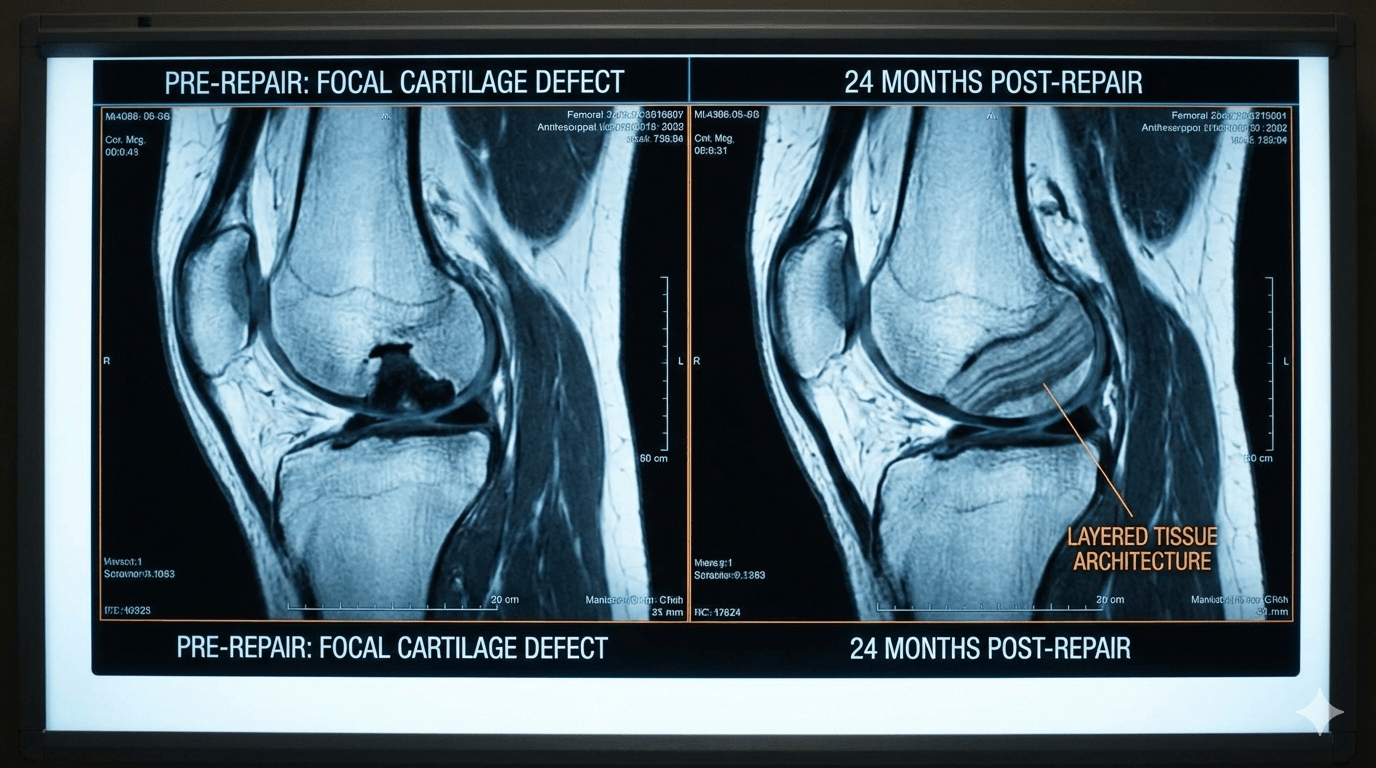

Critically, the MRI results revealed a "layered architecture" comparable to native hyaline cartilage, suggesting the treatment provides a biological restoration rather than the weaker, fibrotic "filler" tissue common in traditional surgeries.

The data, published in the peer-reviewed journal Cartilage, analyzed patients 24 months after receiving GelrinC, a cell-free, off-the-shelf scaffold.

Using the MOCART (Magnetic Resonance Observation of Cartilage Repair Tissue) scoring system—a validated methodology accepted by the FDA and EMA—researchers found a mean score of 88.8 out of 100.